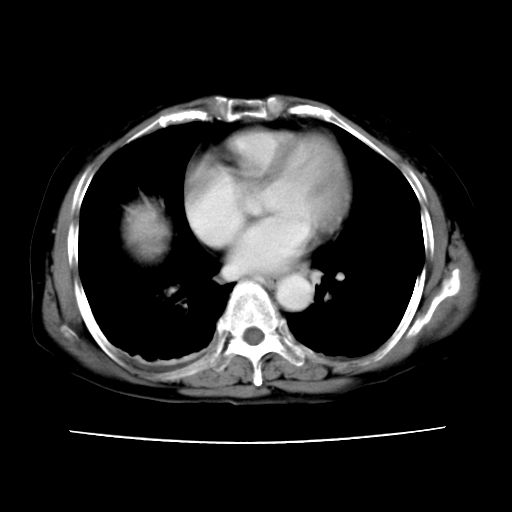

2008-6-10ct平扫

ct增强

6月片:肝血管瘤并破裂出血?肝左外叶囊肿

考虑肝腺瘤出血可能,肝血管瘤增强表现不是很典型,放在第二。

考虑为肝血管瘤破裂出血并肝包膜下血肿;右侧少量胸腔积液。

6月份ct片显示肝内巨大混杂密度团块,伴包膜下积液(内含液液平面),增强多无明显强化。只能考虑肝占位病变,并肝内、血膜下血肿。肝ca并出血多见,而肝血管瘤并破裂出血少见。